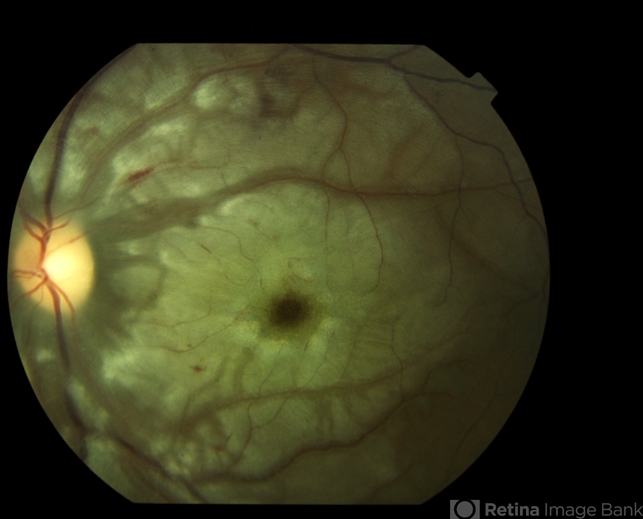

- Purtscher's retinopathy

- Fundus images of a 21-year-old woman with Purtscher's retinopathy. Mild visual improvement 20/200 OU vs. 20/400 OU .